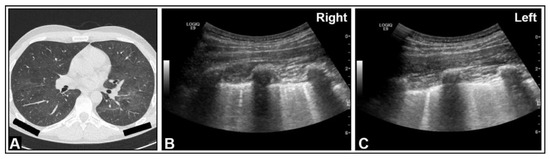

5. Pneumonia